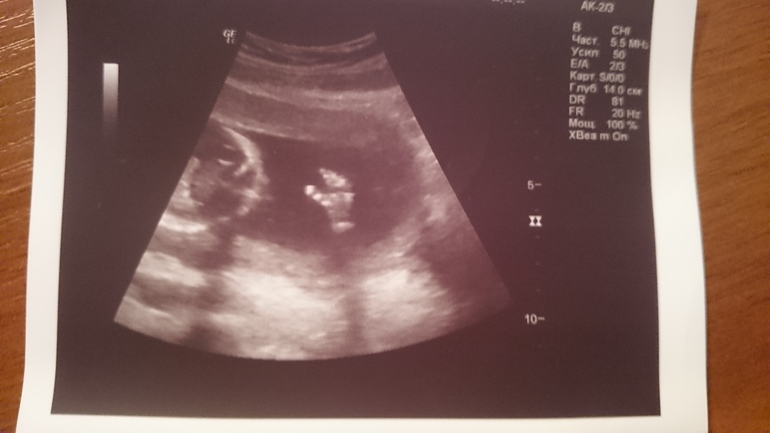

В пятницу ездили в Иваново к моему любимому врачу. Кому интересно, прошу под кат. Они уходят в отпуск на месяц, поэтому я решила съездить, показаться. Конечно же сходили с мужем на узи. У малыша, слава Богу, все хорошо. Мы даже опережаем почти на неделю. Плацента хорошая, до этого нам ставили риск плацентарной недостаточности. Показали все органы, личико, позвоночник, посчитали пальчики. Все на месте, а между ножек большой "пистолетик ". Будет у нас сыночек. Муж сияет, как лампочка! Я всегда хотела девочку, а когда забеременела безумно захотелось сына. Наверное интуитивно почувствовала. Чувствую себя хорошо, только по ночам немеет левая нога, очень не приятно. Врач сказала, что это остеохандроз, такое бывает. Малыш потихоньку пинается. Причём это не похоже на "бабочки " или "пузырики", это такие хорошие мужские пиночки. Вообщем мы очень счастливы! Спасибо Господи!